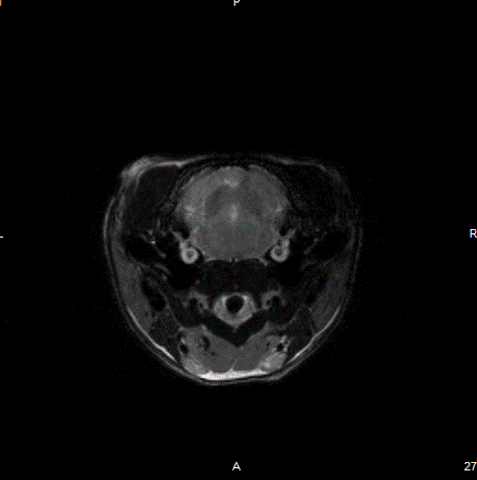

Tumor visualization in various cancer models: Fat-suppressed T2-weighted imaging can be used to detect and quantitatively characterize the growth of a wide range of cancer models

Tumor visualization in various cancer models: Fat-suppressed T2-weighted imaging can be used to detect and quantitatively characterize the growth of a wide range of cancer models. Image Credit: Scintica Instrumentation Inc

Fat-suppressed T2-weighted imaging can be used to detect and quantitatively characterize the growth of a wide range of cancer models.

Fat-suppressed T2-weighted imaging can be used to detect and quantitatively characterize the growth of a wide range of cancer models. Image Credit: Scintica Instrumentation Inc